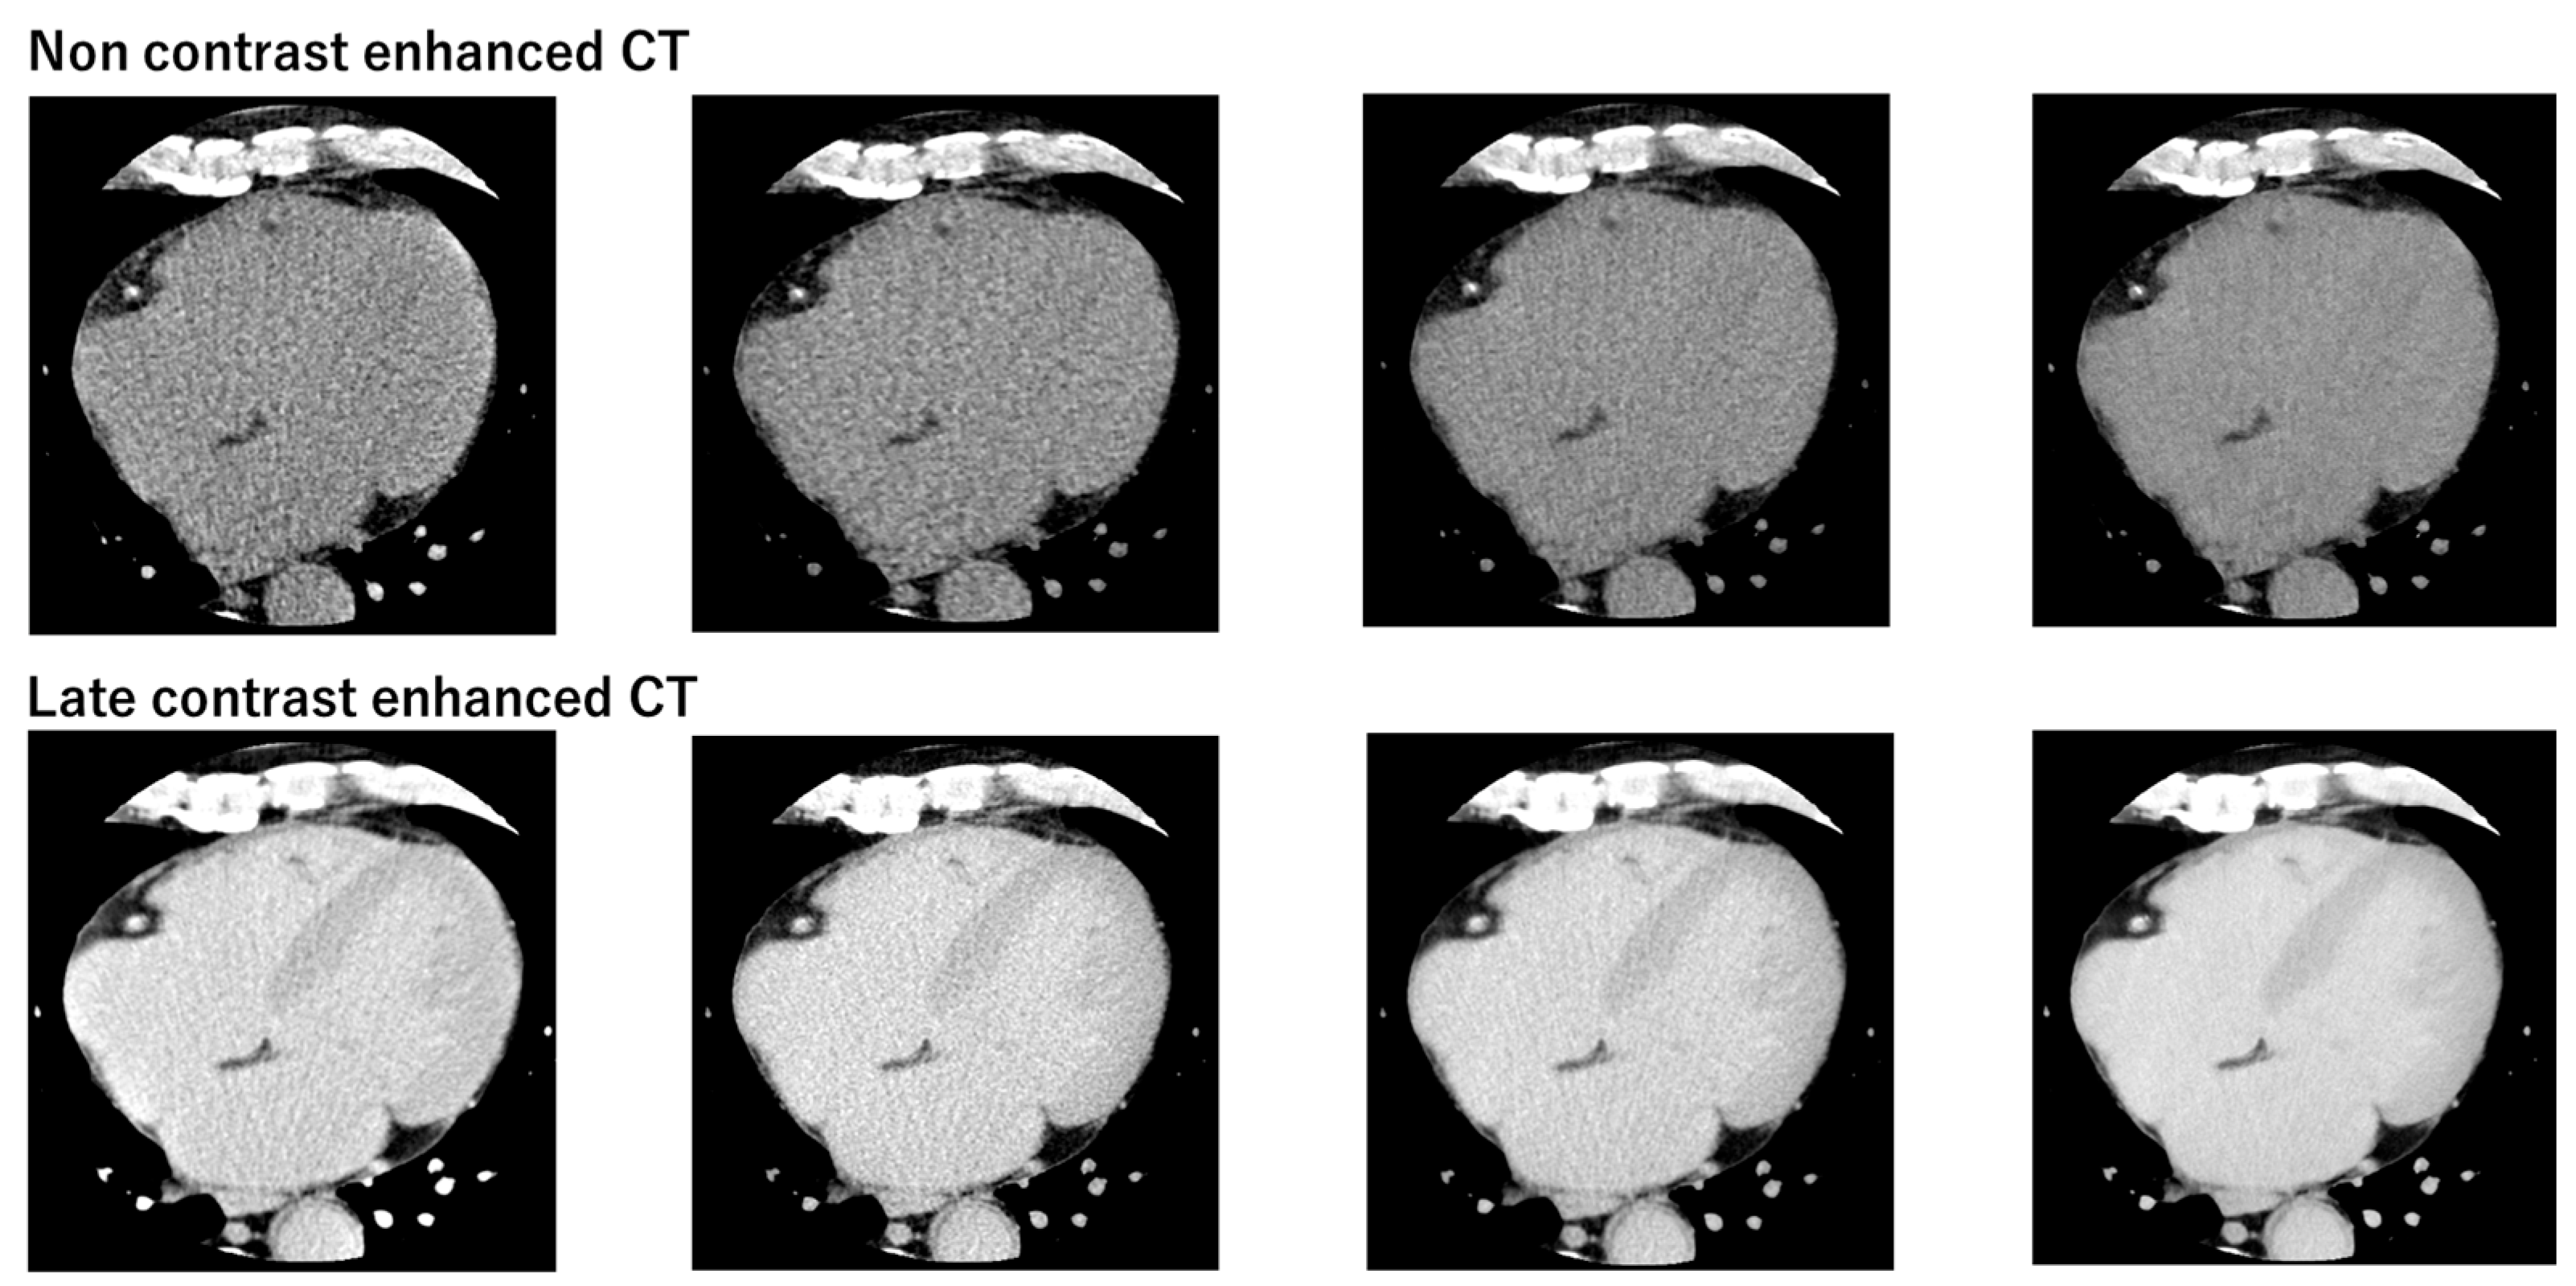

3.3. Comparison of Synthetic ECV and Laboratory ECV across Four Reconstruction Methods in the Validation Cohort